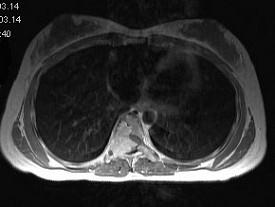

问题 女,18岁,腰以下麻木、双下肢无力,行走困难。PE:双下肢肌力IV+级,肌张力高,腱反射活跃,T以下痛觉消失,深感觉减退,请根据所提供图像,选择最可能的诊断 ( )

选项 A、脊膜瘤 B、淋巴瘤 C、骨母细胞瘤 D、骨巨细胞瘤 E、神经鞘瘤

答案 D